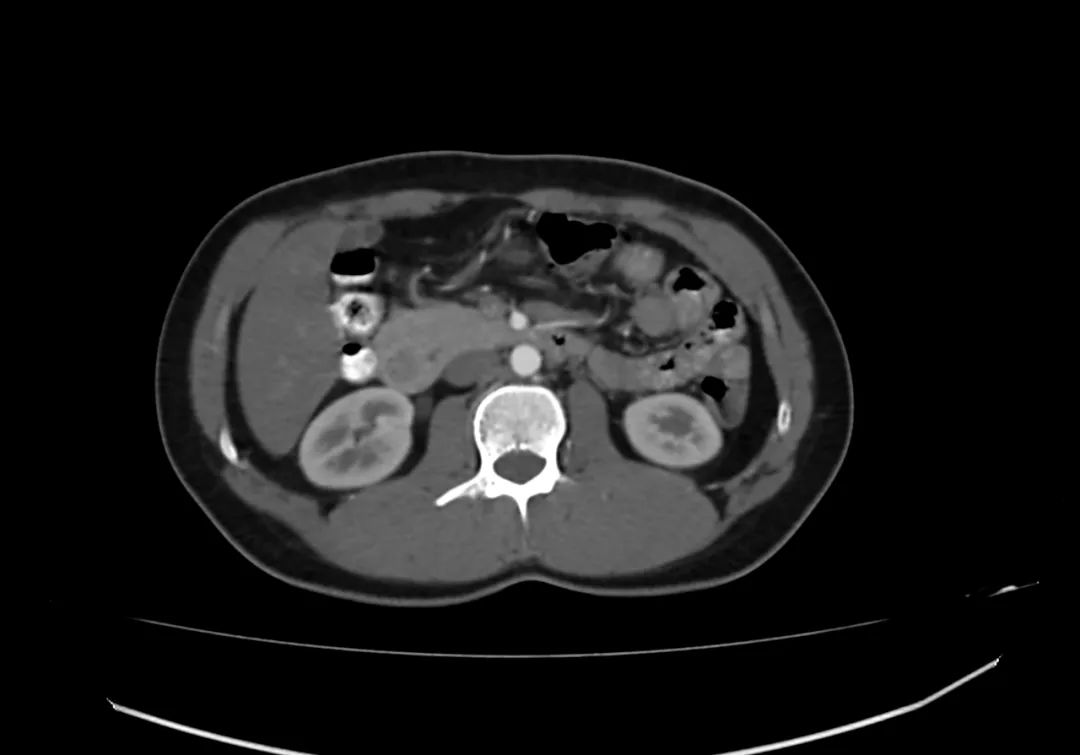

动脉期上腹部轴向增强图像显示胰腺完全包围十二指肠第二部,与完全性环状胰腺一致。